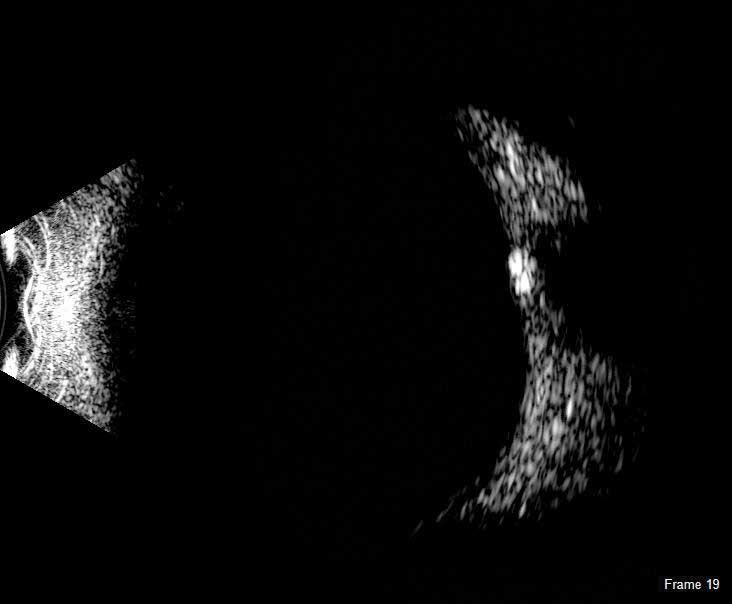

The DGH 8000 B-Scan combines the most advanced ultrasound technology available with the processing power, data storage and connectivity advantages of a personal computer. The DGH 8000 is equipped with dual 12.5 MHz and 15 MHz frequencies in the same probe, which results in a unique depth selection range from 3 cm and 6 cm in 12.5 MHz mode and 5 cm and 10 cm in 15 MHz mode.

It is a self-contained portable imaging system that interfaces with a Windows® computer via a USB 2.0 port. High resolution video loops and still images are obtained rapidly, and post processing features include playback, gain adjustment, contrast and image intensity variation, distortion-free zoom, distance, angle and area measurement and annotation tools. Patient data can be stored on a local computer or on a centralized network location where it can be accessed by multiple users. Patient records are fully searchable and can be exported in a format that is compatible with EMR/EHR systems.

The DGH 8000 B Scan delivers clear images for the posterior portion, even when optical clarity is compromised:

- Retinal Detachments

- Vitreous Detachments

- Vitreous Humor Pathologies

- Staphylomas

- Posterior Segment Pathologies

- Choroidal Pathologies

- Optic Nerve Pathologies

- Scleral Thickening